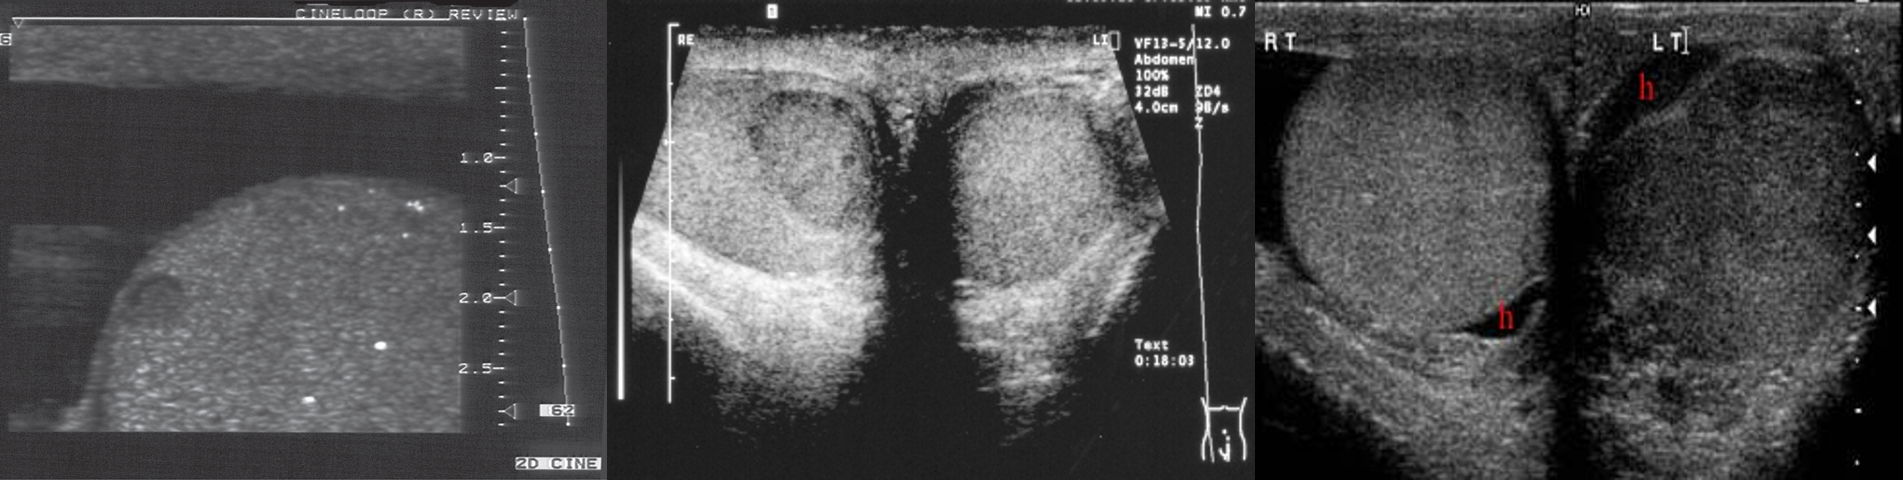

Ultrasound of a testis

demonstrating a small seminoma.

• Several very bright echogenic specks of microcalcification are seen

Reactive Hydrocele 3rd img